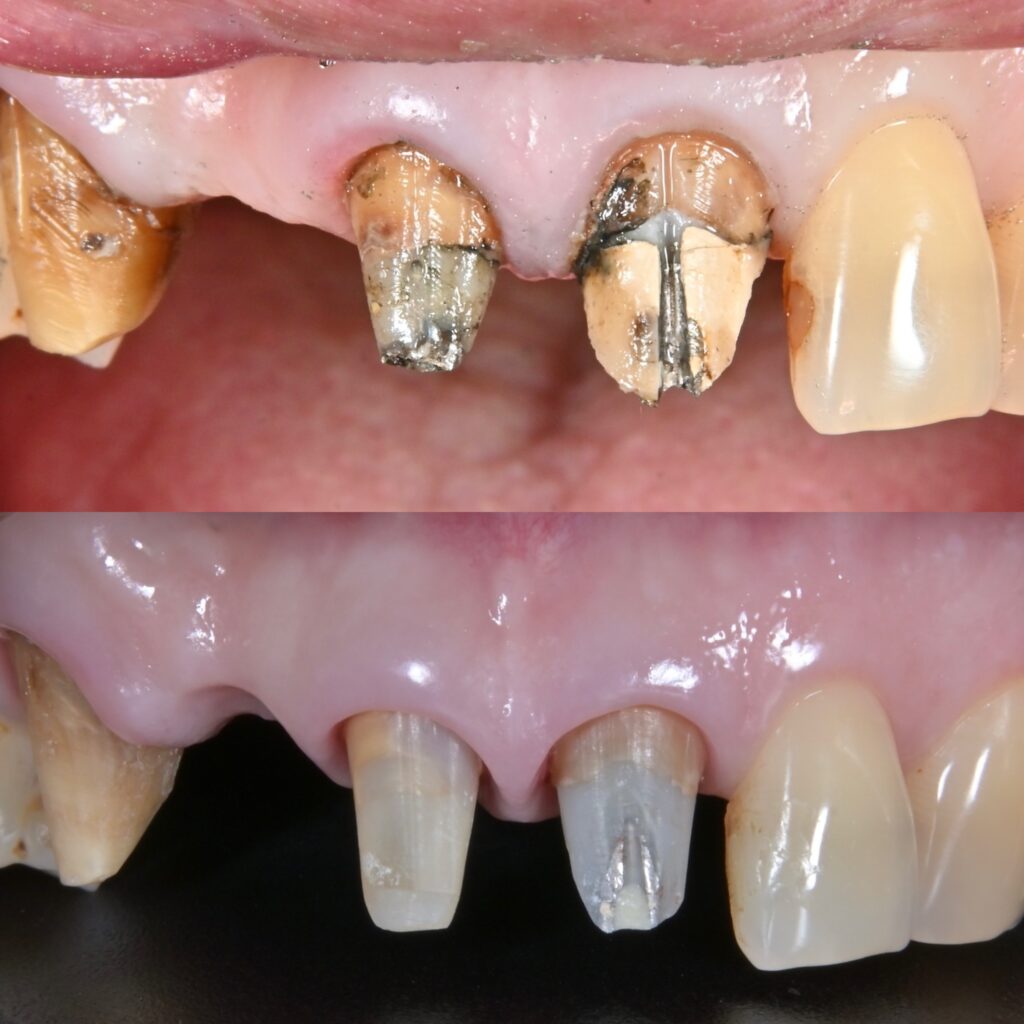

術前術後

1. 「見た目」と「機能」を両立させるための診断

審美歯科において、患者さまの主訴(見た目の改善)を解決するのは当然のことです。しかし、それと同時に重要なのが「機能面」の回復です。

正しく噛めるか、発音を邪魔しないか、そして長持ちするか。これらを実現するために、当院では術前の診断を最も重視しています。